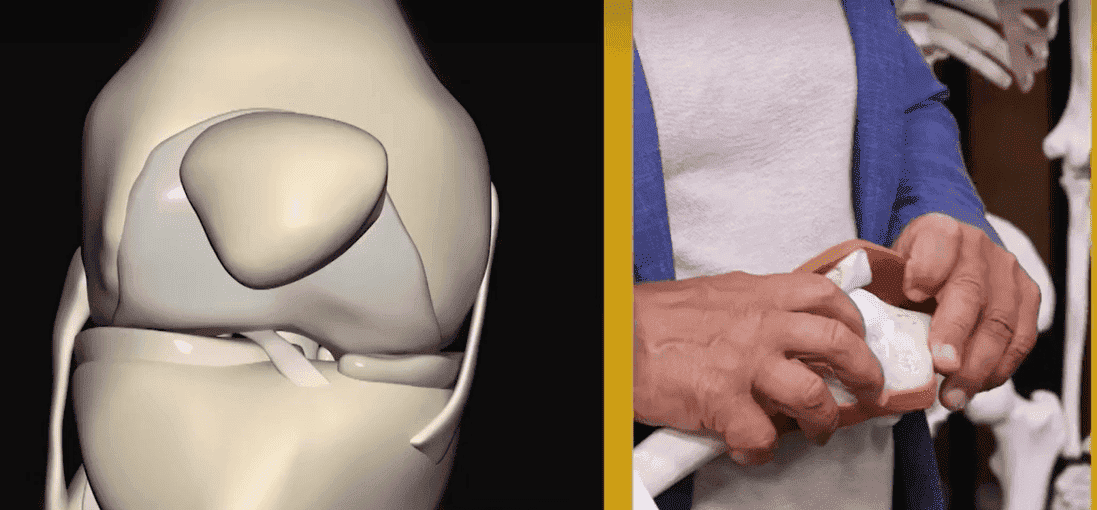

Кореспондент: Защо болят ставите?

Д-р Кристиян Гоновски:

Основната причина за проблеми със ставите и гръбначния стълб е недостатъчното отделяне на

синовиална течност..

Д-р Кристиян Гоновски:

Основната причина за проблеми със ставите и гръбначния стълб е недостатъчното отделяне на

синовиална течност..

Синовиалната течност действа като естествен лубрикант. При липса на синовиална течност

ставите се износват и разрушават. На първо място са засегнати коленете, пръстите, лактите и

гръбначния стълб.

Синовиалната течност е гъста течност, която запълва ставната кухина. Съставът му е подобен на този на плазмата, но съдържа гликани и протеини, които образуват стабилни комплекси с него. Благодарение на тези "компоненти", вискозитет и еластичност, синовиалната течност перфектно изпълнява функцията на вътреставно смазване.

Кореспондент: Колко опасни са ставните заболявания?

Д-р Кристиян Гоновски:

Основните усложнения на ставните патологии са промени във формата на ставите, силно ограничаване

на движението и анкилоза, която напълно обездвижва ставата и я фиксира в положение, често

неправилно..

Д-р Кристиян Гоновски:

Основните усложнения на ставните патологии са промени във формата на ставите, силно ограничаване

на движението и анкилоза, която напълно обездвижва ставата и я фиксира в положение, често

неправилно..

Когато ставите не се огъват и разгъват напълно, осите на крайниците се променят, по

които се разпределя основното механично натоварване върху тялото. Поради систематичното

нарушаване на правилната ос на крайника, натоварването на други стави се увеличава, което

провокира вторични дегенеративни промени.

Д-р Кристиян Гоновски:

това е особено важно, когато става въпрос за носещи тежести стави: коляно, бедро, глезен.

Д-р Кристиян Гоновски:

това е особено важно, когато става въпрос за носещи тежести стави: коляно, бедро, глезен.